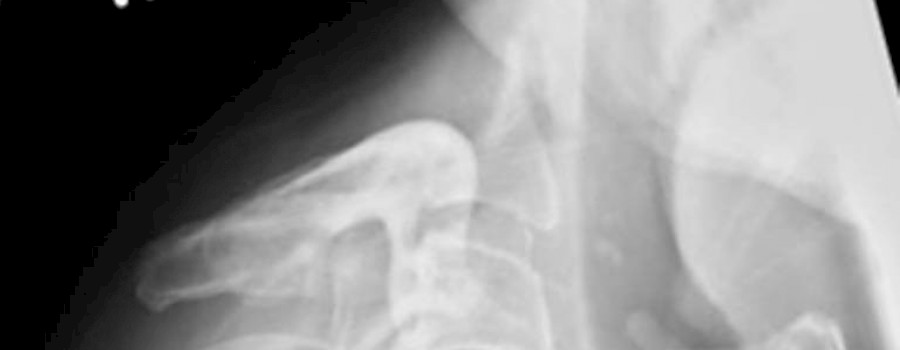

Röntgen HWS seitl. "kopflos" - So könnte die Anforderung für diese Aufnahme der HWS seitlich gelautet haben.

Patient: männlich Alter: 48 Jahre alt - keine relevanten Vorerkrankungen - kommt zur ambulanten Untersuchung.